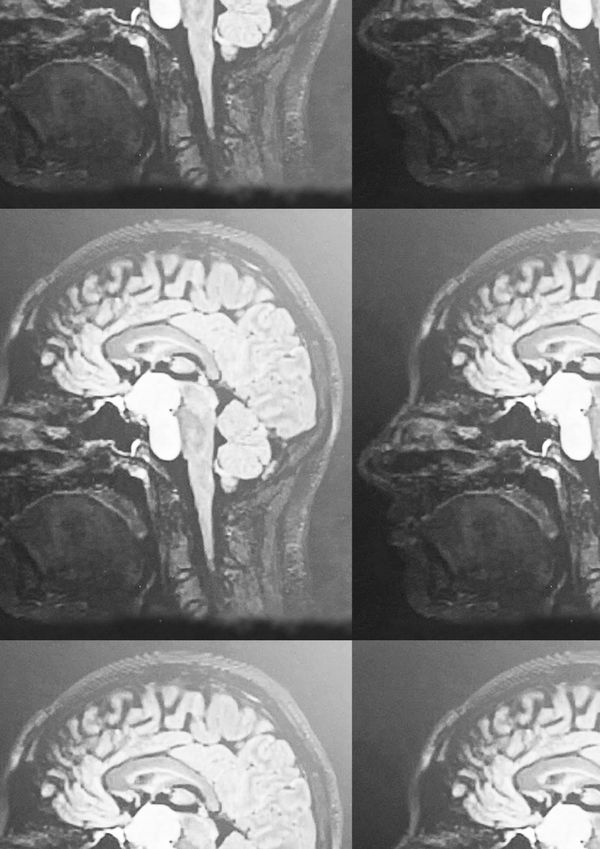

A coming-of-age series navigating a brain tumour diagnosis, surgery and hormonal therapy. Eden's journey through land and water seeks solace within places that have shaped her, questioning 'home', identity and truth. A ritual of hope.

Since her early teens, Eden’s experience has been shaped by extreme hormonal challenges, compulsions, and behavioural shifts. In July 2024, an MRI revealed a large benign brain tumour in the centre of her head, assumed to have been there since childhood. Since it's size and position have made it too complex to remove, she has remained under constant monitoring and must take hormone replacement therapy for the rest of her life.

Over the past year, 'Child of the River' has formed both a personal archive and investigation, as Eden has intutively responded to her diagnosis, biopsy surgery and invasive hospital appointments with her camera. Collecting self portaits, photographic experiments and moments of escape within nature, she has begun to piece together a space of safety and wonder.